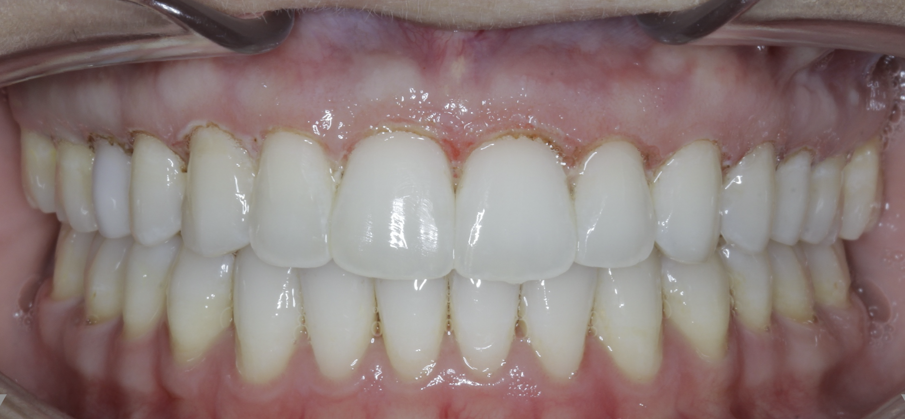

Once the impaction has been completed, the TADs are tied to the wire using steel ligatures and box elastics are used to close the posterior bite (Figs. 19 & 20). To maintain space closure, a tieback module is used from a hook on the mesial to the cuspid to the hook on the first molar and is placed occlusal to the brackets to prevent gingival impingement. Again, a gingivectomy is performed posttreatment to idealise tissue shape and size, and hardtissue contouring is performed (Figs. 21–23, end of treatment).